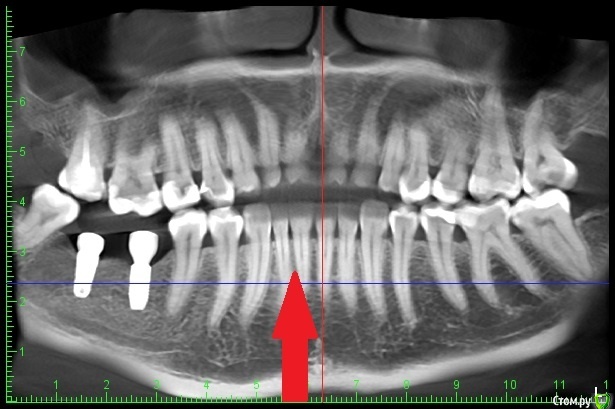

Diana1974 Опубликовано 8 января, 2021 Поделиться Опубликовано 8 января, 2021 Добрый день! Подскажите, нормально ли это и нужно ли просить что-то переделывать? 2 недели назад поставили коронки на импланты, до первого приема пищи всё было хорошо, десна выглядит нормальной, но места установки постоянно ноют, еда очень сильно набивается и также вызывает сильное давление и боль, жесткая еда и холод вызывают пульсацию. Врач сказал, всё хорошо и будет еще затягивать их. Ноющая боль появлялась еще с момента установки формирователей (в июле), но врач также говорил, что всё хорошо прижилось и идет по плану. На втором снимке стрелочкой указала сопутствующую проблему: беспричинная сильная боль и пульсация четко в десне между передними зубами, которая то утихает, то появляется вновь (стоматолог и парадонтолог осматривали, по их части проблем нет, зубы, между которыми боль ни разу не лечились и на данный момент здоровы), проблеме 3 месяца, предпринимала много чего, в итоге меня отправляют к стоматоневрологу. Всё это может быть связано с имплантами или наоборот все эти проблемы не относятся к стоматологии и нужно искать причину у невролога? Ссылка на комментарий

kramer Опубликовано 9 января, 2021 Поделиться Опубликовано 9 января, 2021 Попросите врача проверить все зубы вверху и внизу с этой стороны на предмет пульпита, раз вы говорите, что еще в июле появилось. Ссылка на комментарий

Diana1974 Опубликовано 9 января, 2021 Автор Поделиться Опубликовано 9 января, 2021 Попросите врача проверить все зубы вверху и внизу с этой стороны на предмет пульпита, раз вы говорите, что еще в июле появилось. Скриншоты, которые я приложила в первом сообщении взяты из кт от 23 декабря, врач тогда сказал, что мы его как раз и делаем, чтобы еще раз перепроверить все зубы, долго смотрел и сказал всё хорошо, разве что на дальнем зубе можно переделать запломбированные каналы. Ссылка на комментарий